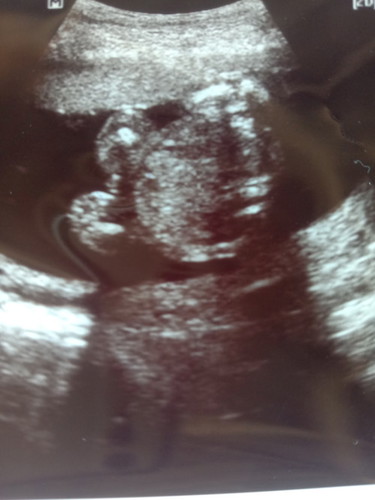

20 สัปดาห์ ไปหาคุณหมอมา อยากทราบว่าในรูปที่ซาวมา ลูกผู้หญิงหรือว่าผู้ชายค่ะ

ดูยากอยู่ค่ะแม่ ก้ำกึ่ง เหมือนกลีบก็เหมือน เหมือนจู๋ก็เหมือน